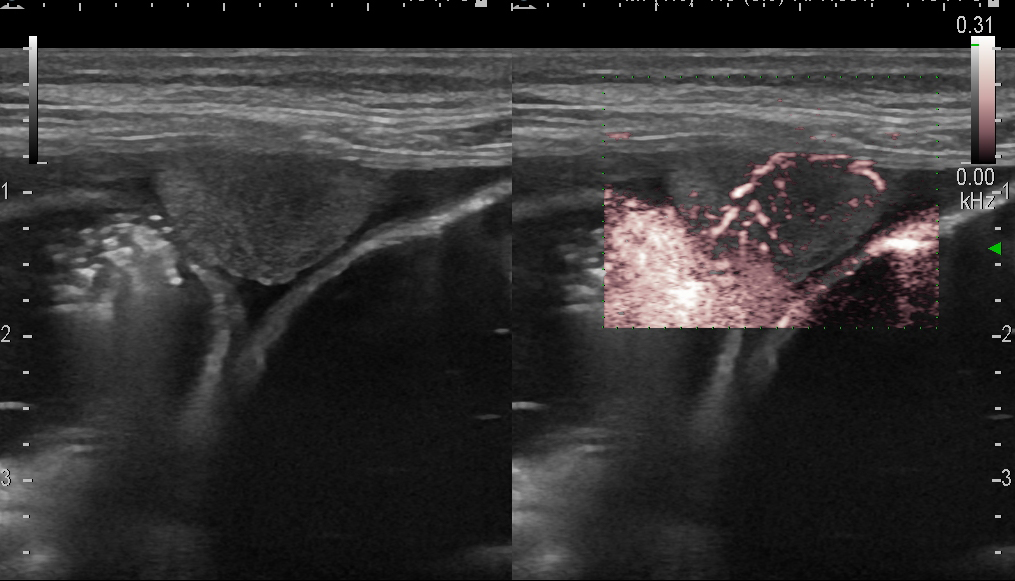

Канцероматоз брюшины у больной с опухолью толстой кишки

canc_0046.jpg

Линейный датчик 7-11 МГц.